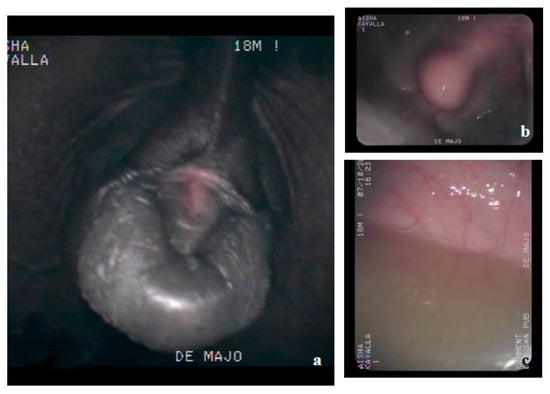

1. Introduction

2.2. Clinical Examination

3.3. Necropsy and Anatomopathological Examination